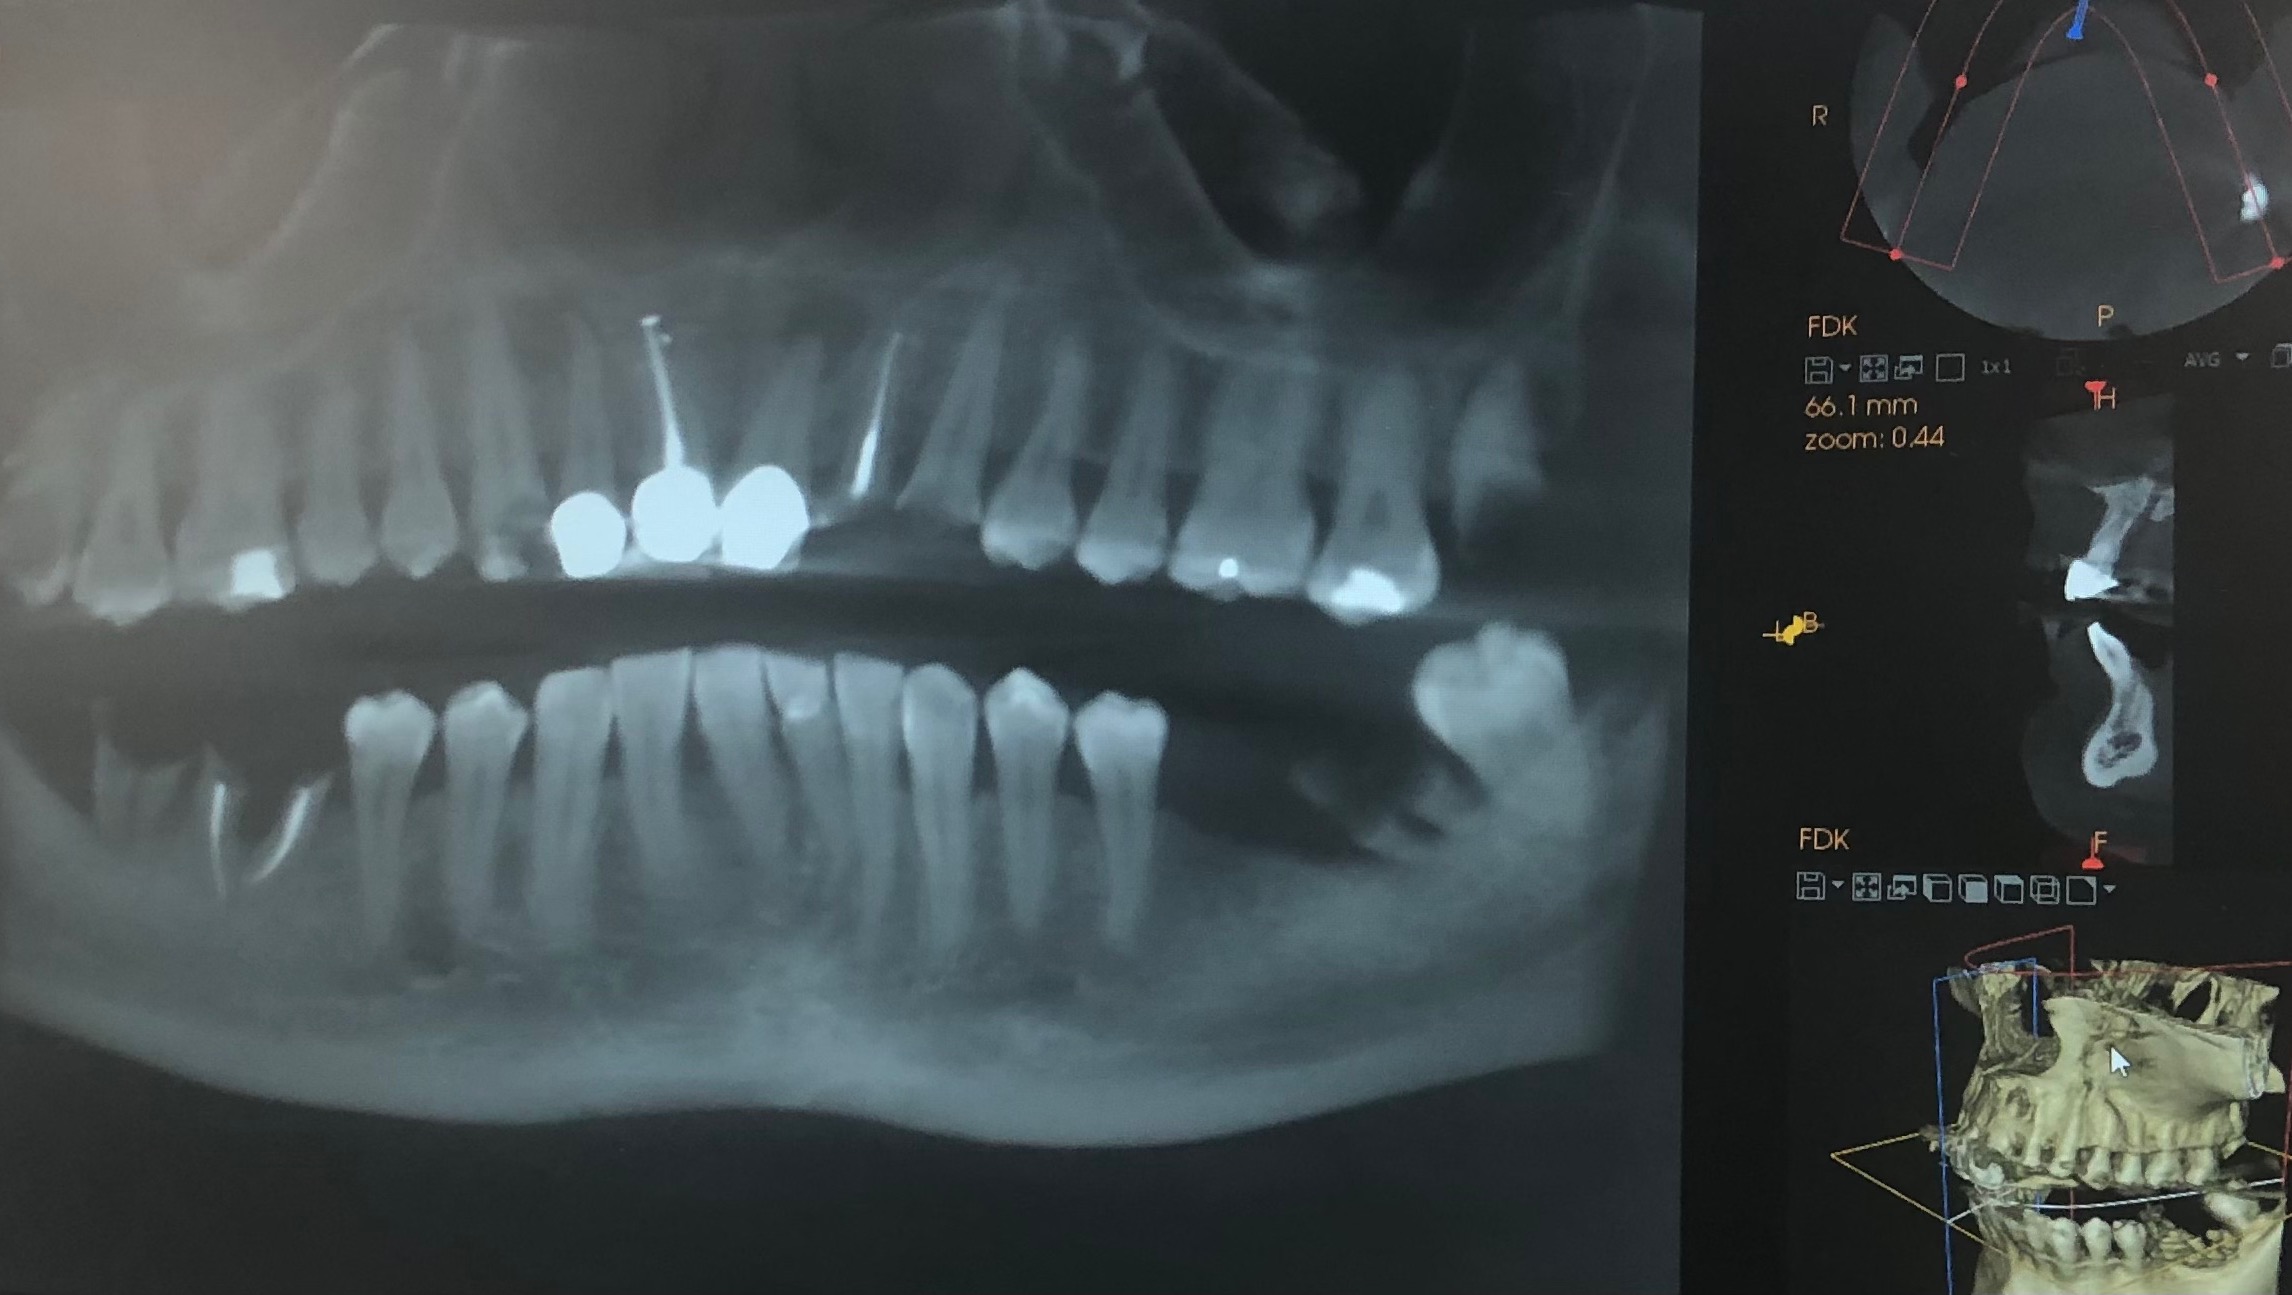

I was born with no enamel, and soft dental spots in my teeth. That led to complications as a child with getting my adult teeth in, and later on lead to a fast deterioration of my smile. Over the years I have had countless tooth infections that cause my face to swell, and pain that I cannot describe. A handful of years ago, I also fell victim to a monster of a man who forced me into anorexia, and other things that cannot be named here. I was able to put him away for life, but to this day I am still dealing with the fallout. My most recent tooth infection led to me finally deciding to make another consultation for the procedure I need done. During that appointment I had an X-ray done, and a partial skull 3D image mapping. This is when I found out just how serious my case was. They found that what I though was one infection, was actually five, that two of the infection had actually started to eat away at the bone of my skull, and that the trauma I had endured from that monster left me with a fracture in my skull that is causing an even faster decay of my teeth. The end of my consultation I was left with the knowledge that I should, for all intents and purposes, not be alive any longer. I can no longer put off this procedure due to the severity of my condition. Essentially, my next infection could be my last. It was a startling and heart stopping moment for me.

Some photos of what a tooth infection looks like for me, as well as the latest X-ray of my teeth..